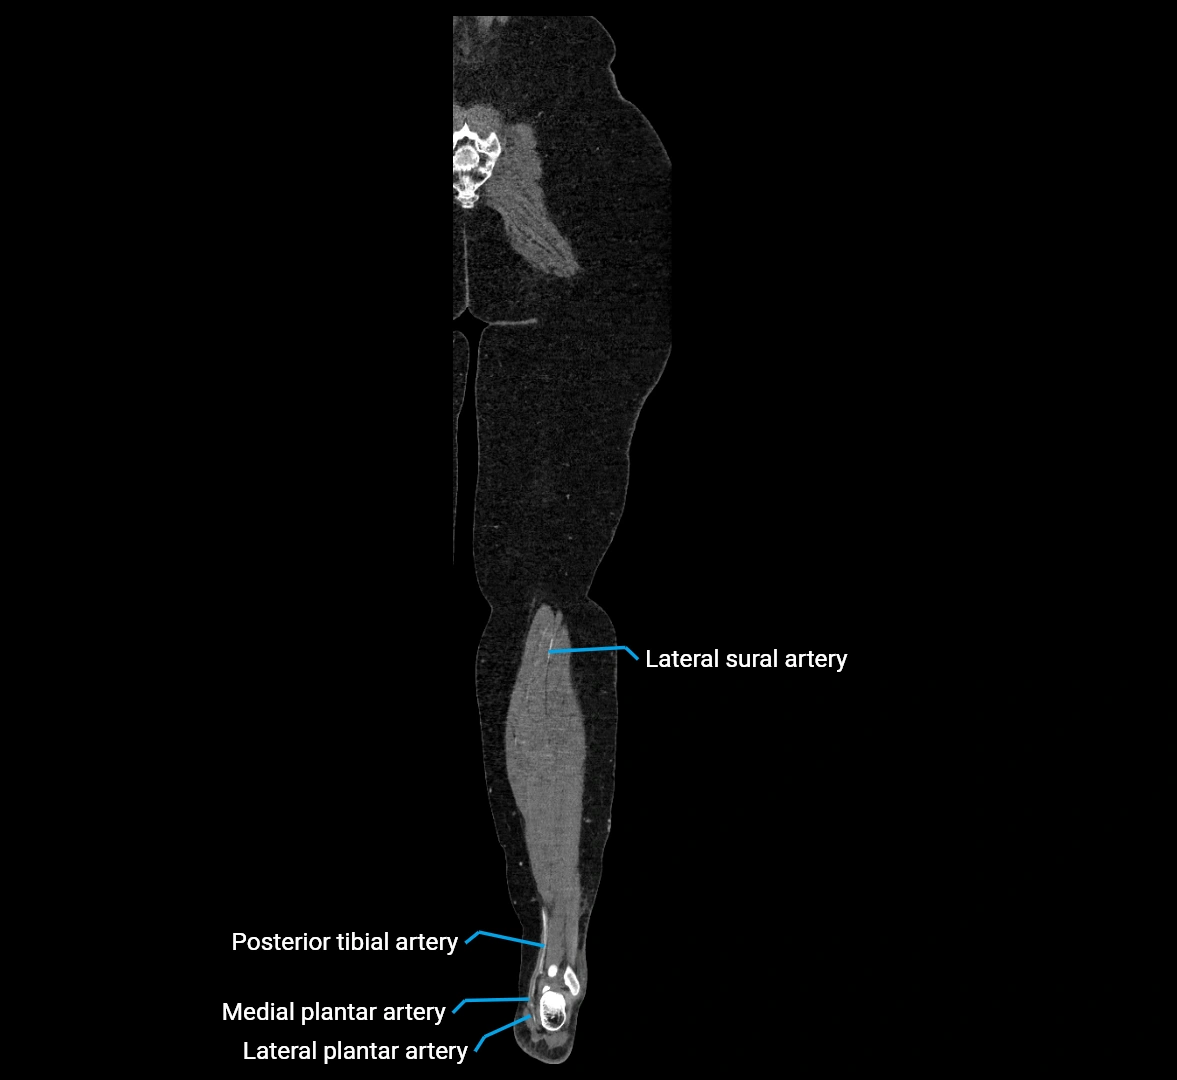

CT Appearance

Non-contrast CT:

• Appears as a tubular soft tissue structure anterior to vertebral bodies

• Calcified atherosclerotic plaques appear as hyperdense foci along the wall

• Useful for screening abdominal aortic aneurysm (AAA) size and mural calcification

Contrast-enhanced CT (CTA):

• Gold standard for abdominal aortic imaging

• Provides excellent detail of lumen, wall, aneurysm, thrombus, and branch vessels

• Multiplanar and 3D reconstructions help in aneurysm measurement, stent graft planning, and dissection evaluation

• Detects acute rupture, traumatic injury, or occlusion with high sensitivity

CT images

image